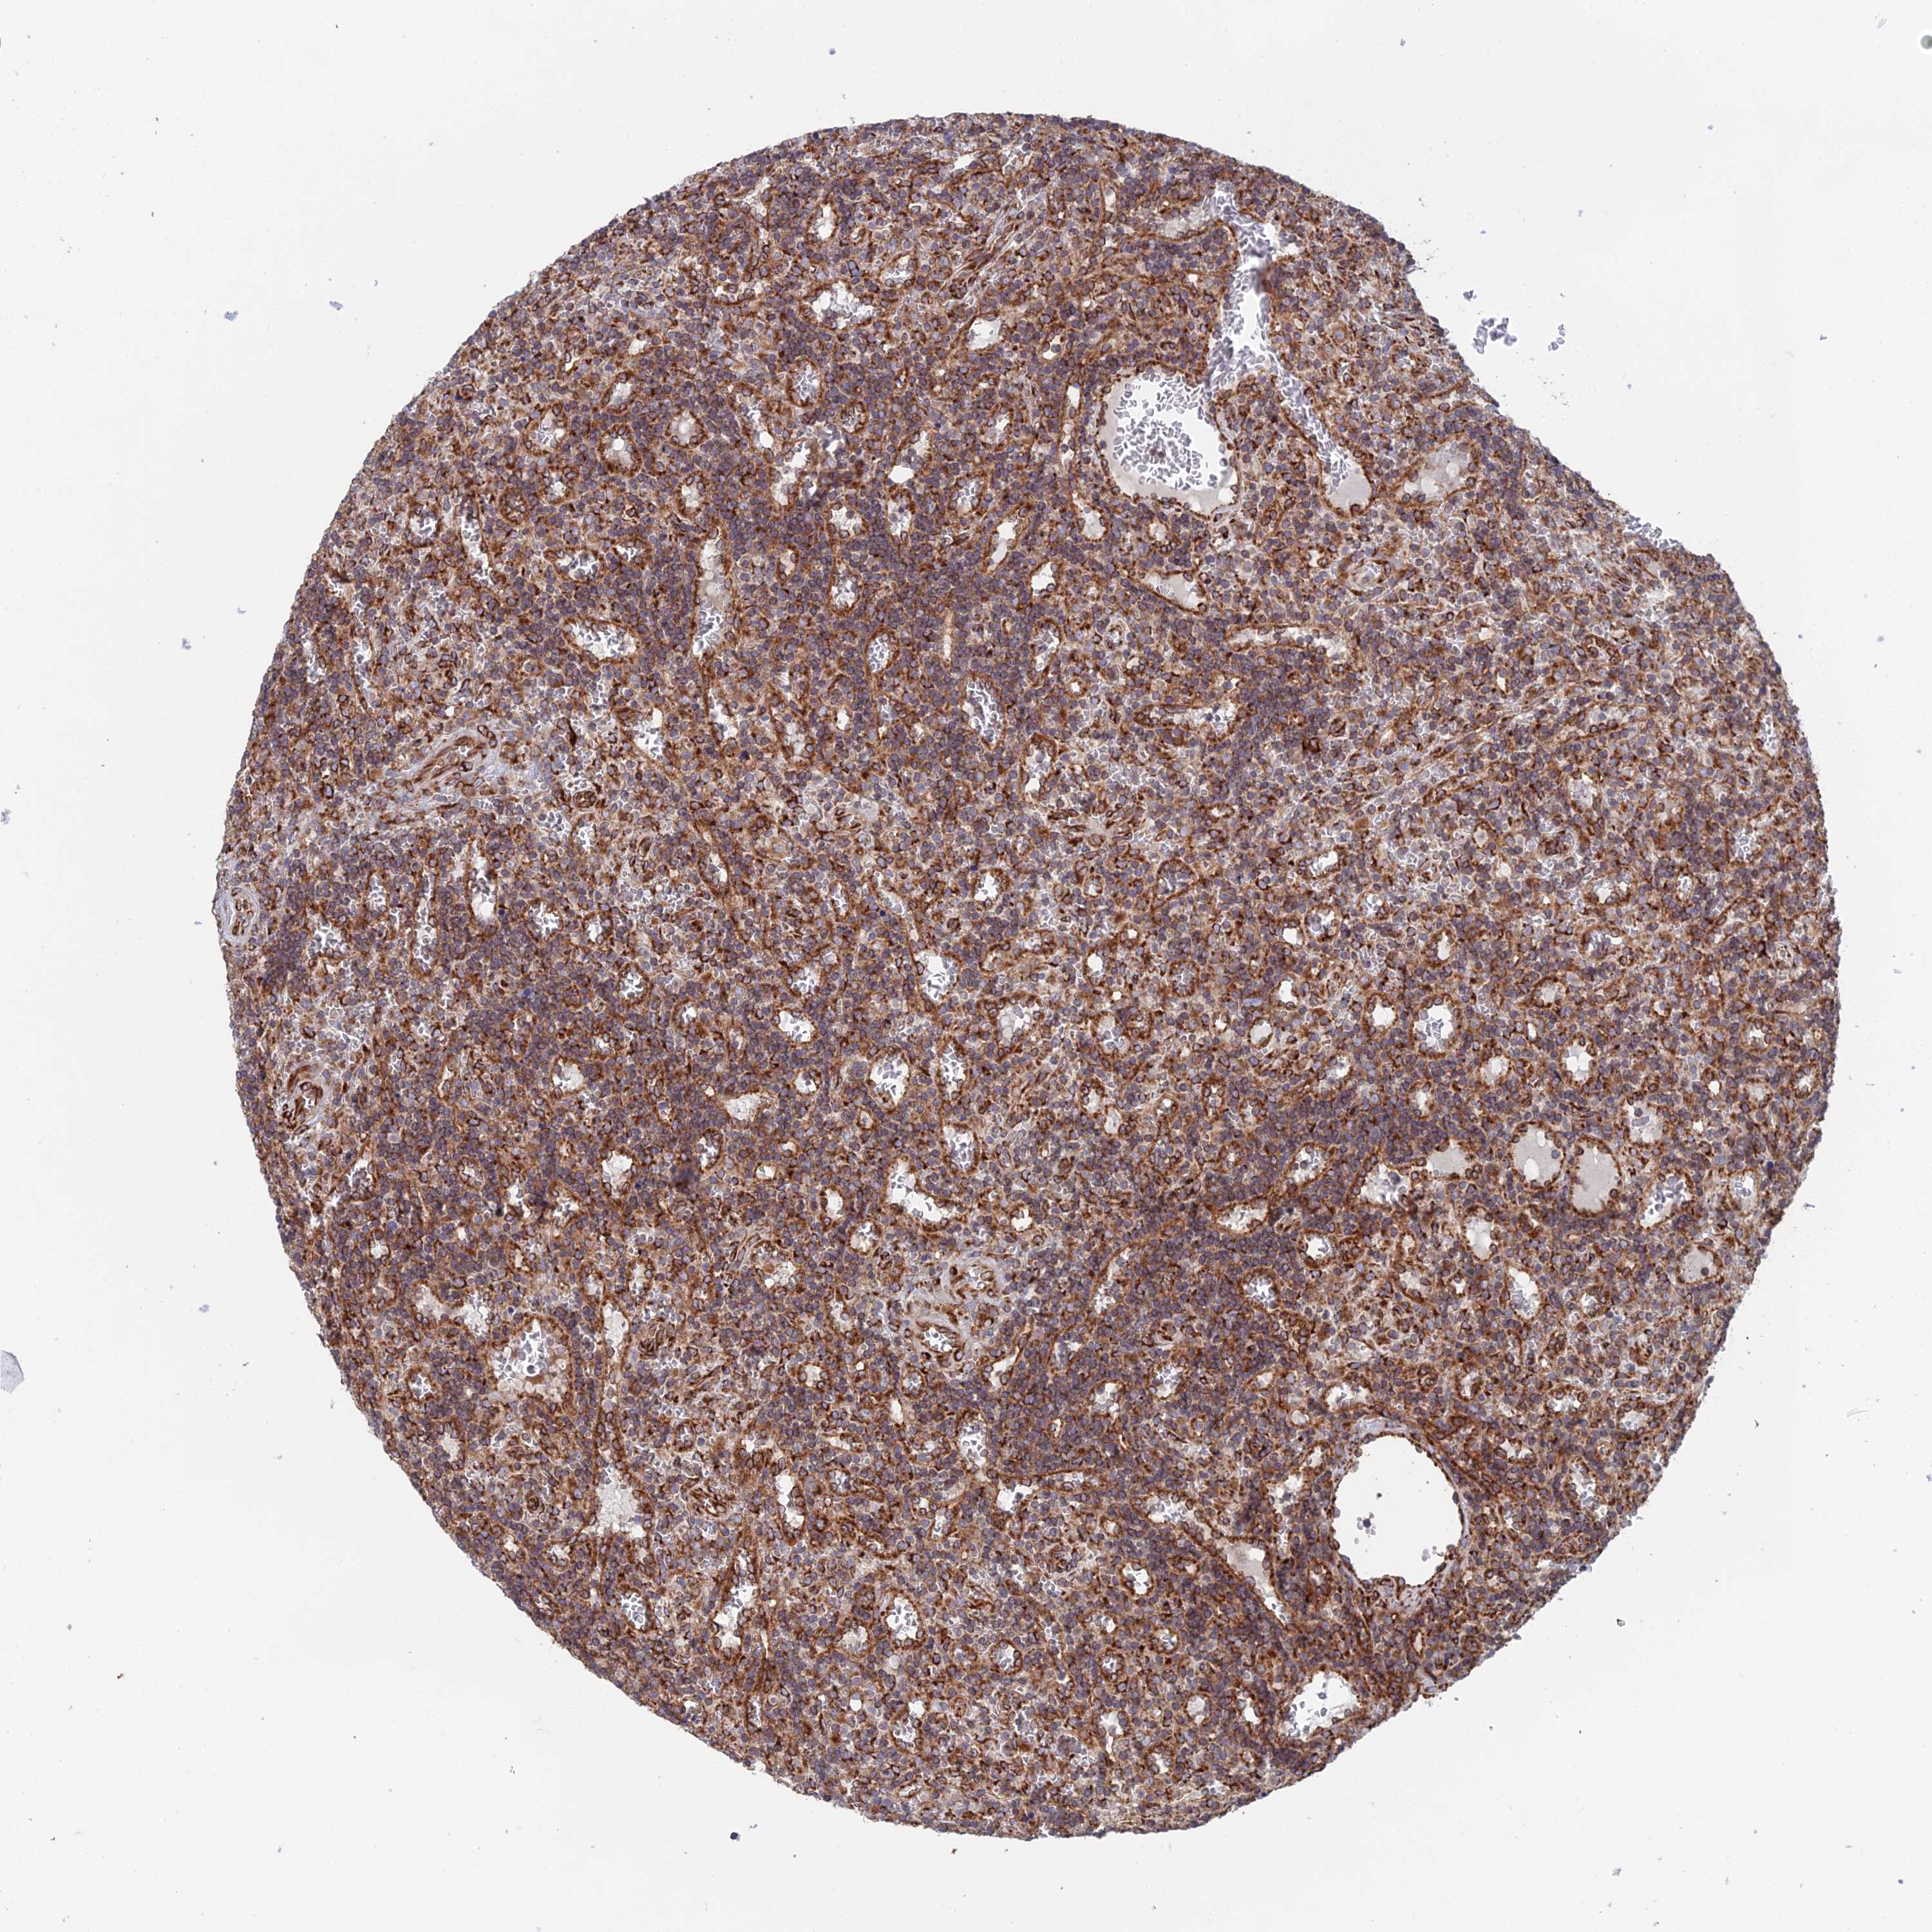

CANCER LYMPHOMA Show tissue menu

LYMPHOMA - Protein expressioni

A mouse-over function shows sample information and annotation data. Click on an image to view it in a full screen mode. Samples can be filtered based on level of antibody staining by selecting one or several of the following categories: high, medium, low and not detected. The assay and annotation is described here.

Antibody stainingi

Antibody staining in the annotated cell types in the current human tissue is reported as not detected, low, medium, or high, based on conventional immunohistochemistry profiling in selected tissues. This score is based on the combination of the staining intensity and fraction of stained cells.

Each image is clickable and will lead to virtual microscopy that enables deeper exploration of all samples and also displays staining intensity scores, fraction scores and subcellular localization as well as patient and tissue information for each sample.

Antibody HPA043648

Staining

High

Intensity

Strong

Quantity

>75%

Location

Nuclear

Hodgkin's disease, NOS

Malignant lymphoma, non-Hodgkin's type, High grade

Malignant lymphoma, non-Hodgkin's type, Low grade